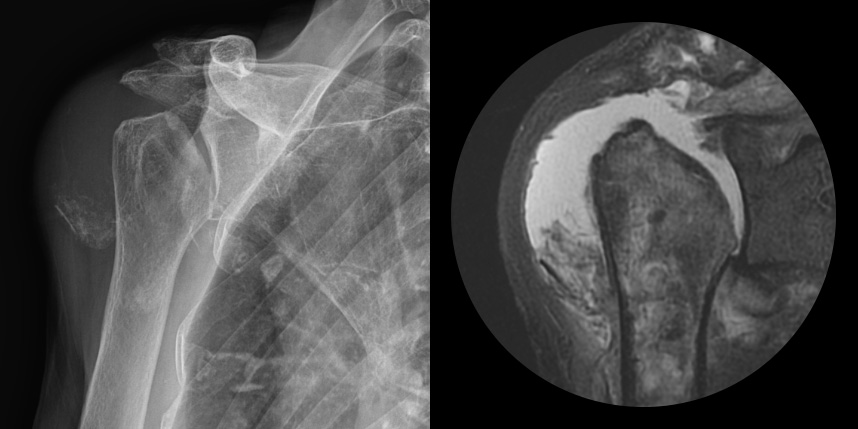

삼하게 망가져 거의 기능이 없는 관절을 제거한 후 특수하게 제작된 인공관절을 삽입하는 수술

비수술 치료에도 호전이 없는 경도의 관절염에서 시행합니다.

역행성 인공관절 전치환술

역행성 인공관절 진치환술

(회전근개 심한 파열 및 관절염 진행)